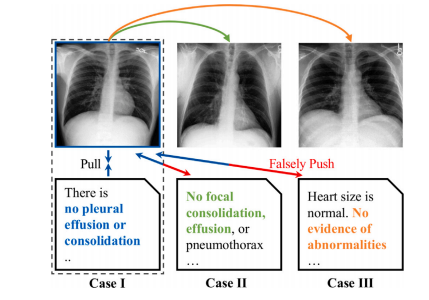

Fig. 8. Illustration of false-negative pairs (Liu et al., 2023a). In CLIP pre-training, apositive pair is defined as an image and its corresponding report, whereas all otherreports are considered negatives. This can result in false negatives, where semanticallysimilar reports from different subjects are mistakenly considered as negative pairs.

图8:假阴性对的图示(刘等人,2023a)。在对比语言-图像预训练模型(CLIP)的预训练过程中,正样本对被定义为一张图像及其对应的报告,而所有其他报告则被视为负样本。这可能会导致假阴性情况的出现,即来自不同主体但语义相似的报告被错误地认定为负样本对。